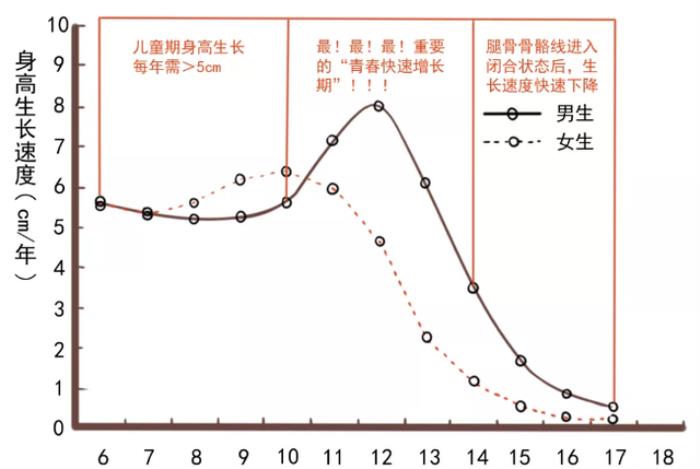

1.发育变缓、慢慢长胖

一般孩子的生长是具有一定规律的,进入青春期后每年身高也会增长6-7cm。如果孩子身高在增长速度上出现突然放缓的现象,就说明骨骺线已经进入闭合状态。当身高增长变得缓慢,营养的持续供给会导致孩子出现横向发育,开始长肉变胖。如果开始出现这两种情况,就要多注意了。

在进入青春期以后,身体也会出现各种各样的变化,当第二性征出现时,比如男孩长胡子、变声、有喉结等,也是预示着骨骺线将要闭合。